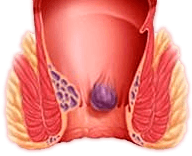

La cosa principale del problema delle emorroidi è che in nessun

caso dovrebbe essere trascurato. Non appena compaiono i primi

sintomi, è necessario iniziare a combattere il problema. Lo

stile di vita e la nutrizione sono importanti, ma se i sintomi

delle emorroidi sono già comparsi, solo queste misure non

aiuteranno. Se non ti accorgi in tempo, purtroppo, solo la

chirurgia può aiutare. Il gel Proctowell è ottimo perché, grazie

alla sua composizione naturale, aiuta a sbarazzarsi dei sintomi

nel modo più naturale possibile. La sua efficacia è confermata

dai riscontri positivi dei miei pazienti. Che hanno per sempre

dimenticato il problema!